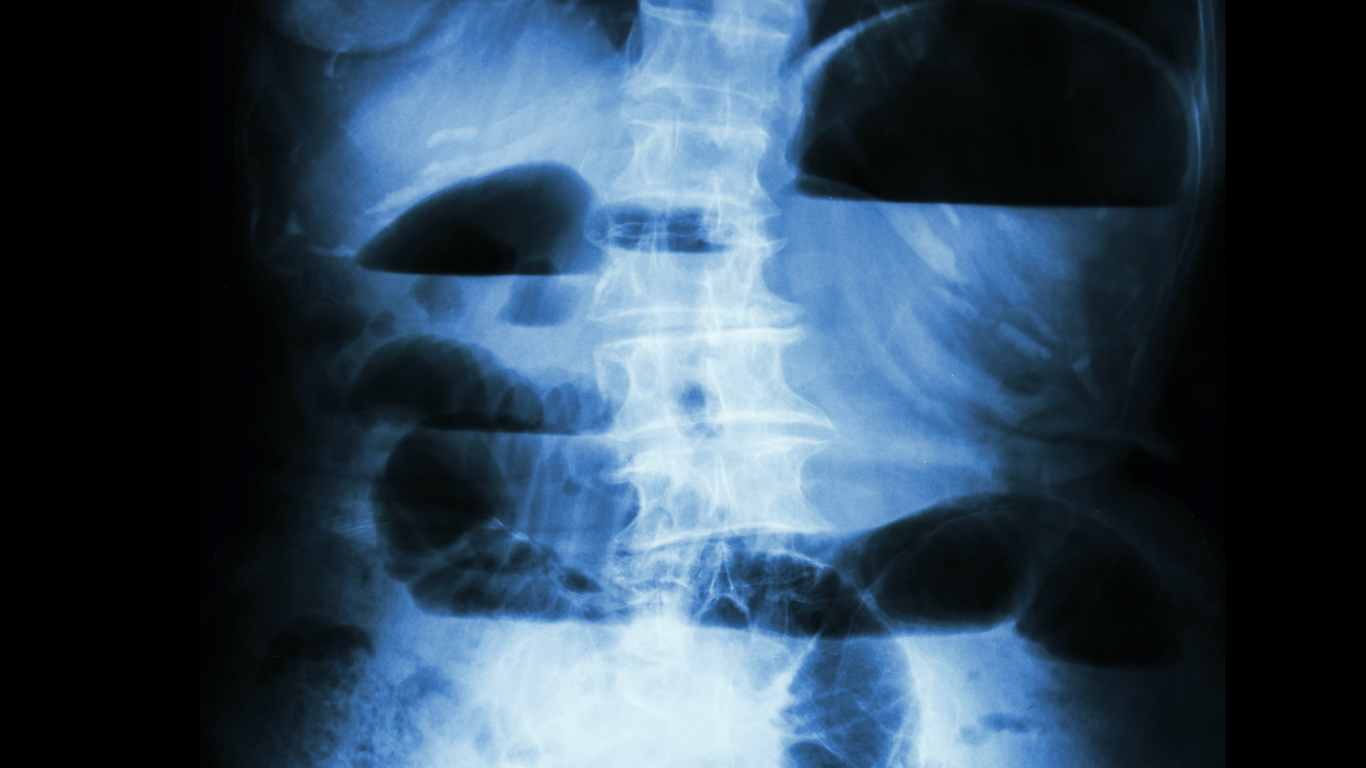

The Science Of The Closed Loop Obstruction

When the bowel is obstructed in two adjacent places, it is known as a closed loop obstruction. In the case of a distal large bowel obstruction, if the ileocecal valve is competent, it creates a sealed loop. The mechanics of closed loop obstruction In any bowel obstruction, above the level of the obstruction, there is Continue reading